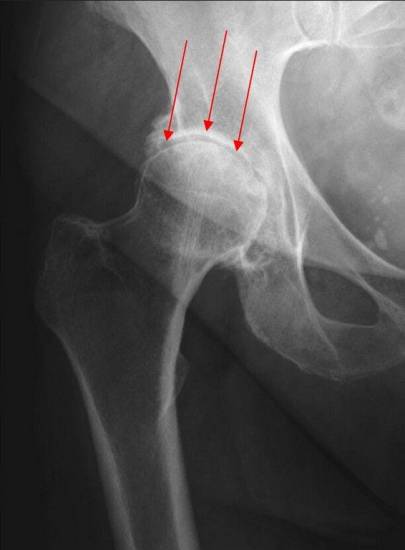

1. Коксартроз — это артроз тазобедренного сустава, причиной которого часто служат дегенеративные изменения связанные с возрастом. «Возрастной» износ сустава встречается у людей старше 50 лет, часто имеющих семейную историю артрита. У таких пациентов истончается и повреждается хрящевая поверхность, возникает трение костей в суставе, что приводит к их повреждению. Степень разрушений в суставе влияет на выраженность боли и ограничение подвижности.

2. Асептический некроза головки бедренной кости — это разрушение головки бедренной кости в результате нарушения кровообращения внутри кости. Отсутствие должного притока крови приводит к разрушению поверхности кости и преждевременному износу сустава.

- Рентгенографию пораженного сустава в разных проекциях;